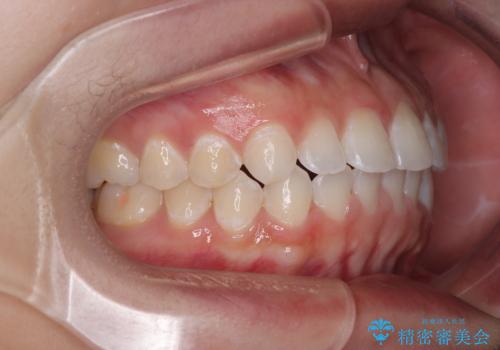

- 上下前歯のデコボコを気にして来院された患者様です。

ワイヤー矯正でもマウスピース矯正でも可能でしたが、短期間で、自身の手を煩わせることなく治療を行いたいとのことで、ワイヤー装置にて矯正治療を行うこととしました。

僅か半年強、あっという間に治療を終えることができました。